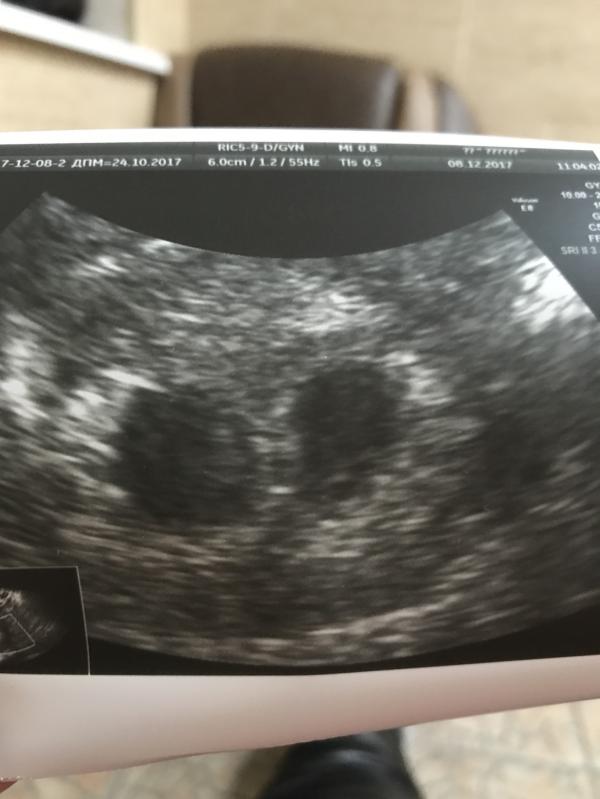

Я просто счастлива и спокойна после УЗИ) Детки мои здоровы и развиваются как надо🙏🏻 Пока пол двойняшек не знаю,но это не главное !